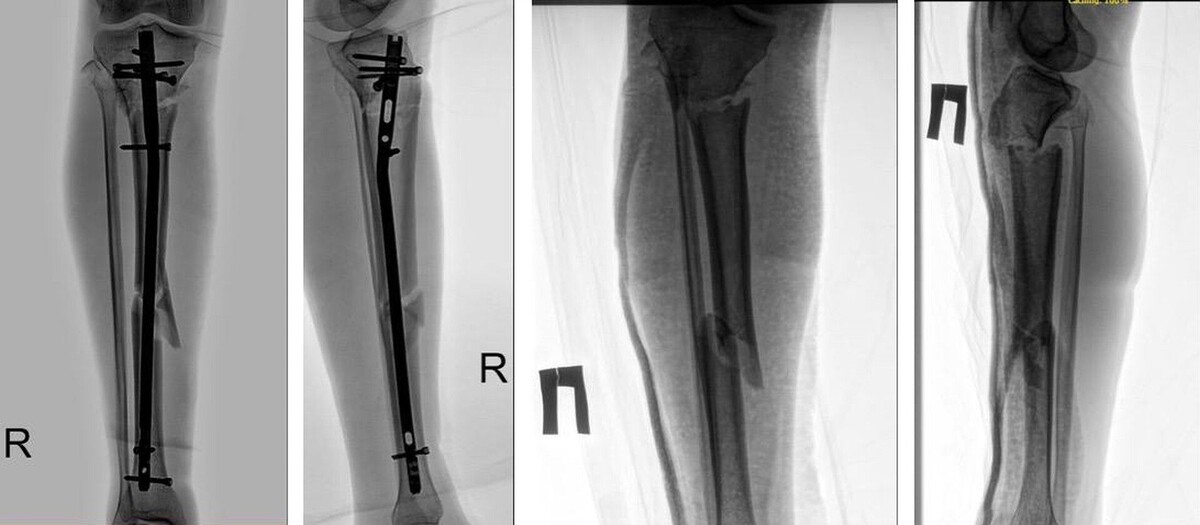

Врачи в Ставрополе провели сложную операцию 36-летнему мужчине, который получил серьезную травму ноги в автоаварии. Об этом сообщается в телеграм-канале медучреждения. После ДТП пострадавшего с ушибом грудной клетки и переломами правой ноги доставили в медучреждение в городе Ипатово. Затем пациента перевели для специализированного лечения в больницу скорой медпомощи краевой столицы. Ставропольские медики спасли мужчине ногу. Хирург Аслан Эсеналиев при ассистировании Давида Фарсяна выполнил интрамедуллярный блокируемый остеосинтез правой малоберцовой кости. После стабилизации состояния пациента выписали и отправили на амбулаторное лечение.

Ставропольские медики спасли мужчине ногу. Хирург Аслан Эсеналиев при ассистировании Давида Фарсяна выполнил интрамедуллярный блокируемый остеосинтез правой малоберцовой кости.